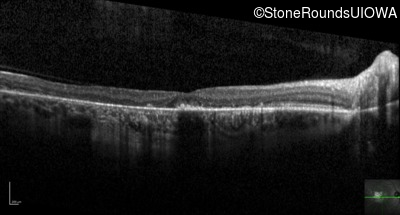

Optical Coherence Tomography - Right - 20/40

Exemplar / OCT Stack